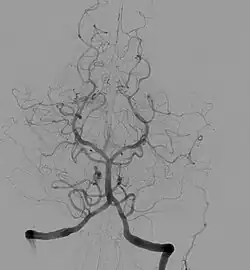

Angiografia cerebral, injeção na artéria vertebral esquerda, com fluxo retrógrado na artéria vertebral contralateral, na artéria basilar e na artéria comunicante posterior. A circulação cerebral posterior pode ser vista, incluindo a parte posterior do Círculo de Willis.